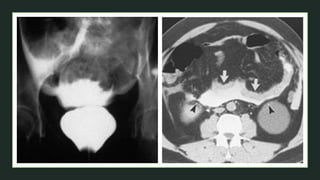

 Stage Ta or T1: An intact, low T2 signal intensity muscle layer at

the base of the tumor is indicative of nonmuscle invasive bladder

tumor.

 Stage T2: Muscle invasive tumor is suggested when the normal

low T2 signal of bladder wall muscle is interrupted by intermediate

T2 tumor signal.

 Stage T3a (microscopic perivesical invasion) diagnosis is

difficult.

 Stage T3b: A bladder wall lesion with an irregular, shaggy outer

border and streaky areas of the same signal intensity as the tumor

in perivesical fat.

Stage Ta or T1

Stage T2

Stage T3b

Stage T4

z  Stage Taor T1: An intact, low T2 signal intensity muscle layer at the base of the tumor is indicative of nonmuscle invasive bladder tumor.  Stage T2: Muscle invasive tumor is suggested when the normal low T2 signal of bladder wall muscle is interrupted by intermediate T2 tumor signal.  Stage T3a (microscopic perivesical invasion) diagnosis is difficult.  Stage T3b: A bladder wall lesion with an irregular, shaggy outer border and streaky areas of the same signal intensity as the tumor in perivesical fat.